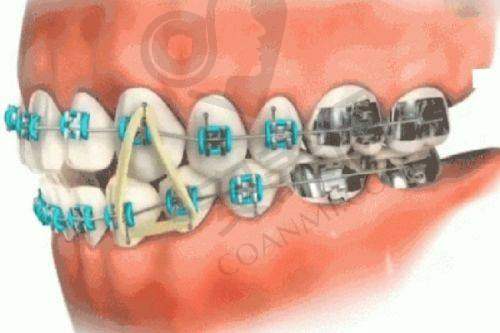

其次,他掌握了多种精良的矫正技术。如金属直丝自锁矫正,这种矫正器自带锁扣,可有效减少调整次数,缩短矫正周期,让患者更快拥有理想的牙齿。数字化隐形正畸则具有美观、舒适、可自行摘戴等优点,适合对美观要求较高的患者。

再者,他注重预防性正畸和综合性方案制定。在矫正过程中,他会考虑到患者牙齿的未来发展情况,提前预防可能出现的问题。同时,他会综合考虑患者的口腔健康、咬合功能等因素,制定全方面的矫正方案,确保矫正成效的长期稳定性。